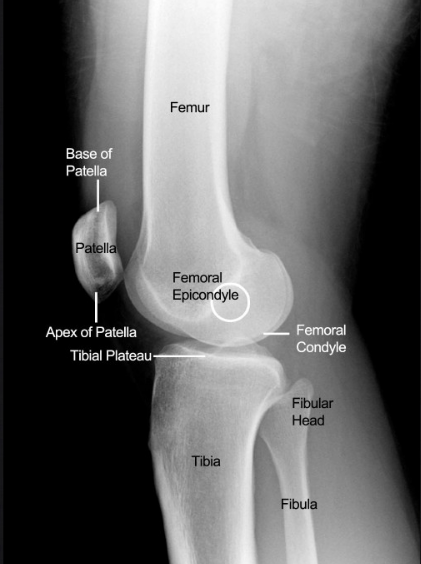

Lateral X-ray of the knee

Normal

© Mr Gavin Holt :: CotswoldClinics.com :: Print this frame